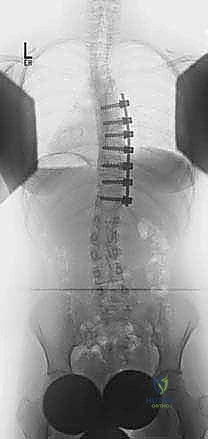

2. التصوير بالأشعة السينية (X-Rays)

هو المعيار الذهبي لتشخيص الجنف. يتم التقاط صور شعاعية لكامل العمود الفقري (من الرقبة إلى الحوض) من الأمام والخلف والجانب، والمريض في وضع الوقوف. من خلال هذه الصور، يقوم الدكتور هطيف بـ:

* قياس زاوية كوب (Cobb Angle): وهي الزاوية التي تحدد شدة الانحناء. الانحناءات الأكبر من 10 درجات تُعتبر جنفاً.

| التدخل الجراحي (الدمج الفقري) | انحناءات شديدة (أكبر من 45-50 درجة)، أو انحناءات تتدهور بسرعة رغم استخدام الحزام. | تصحيح التشوه، دمج الفقرات لمنع التدهور المستقبلي، واستعادة التوازن. | إجراء الجراحة بأعلى معايير الأمان العالمية باستخدام تقنيات متقدمة. |

- الحفاظ على مستويات الحركة (Saving Motion Segments): هذه هي الميزة الأهم! في النهج الخلفي، قد يضطر الجراح لدمج عدد كبير من الفقرات. أما في النهج الأمامي، ولأن التصحيح أقوى، يمكن للأستاذ الدكتور محمد هطيف دمج عدد أقل من الفقرات، مما يترك للمريض مرونة وحركة أكبر في ظهره بعد الجراحة.

- معدلات دمج عظمي أعلى: إزالة القرص الفقري بالكامل ووضع الطعم العظمي في هذه المساحة الكبيرة الواسعة يوفر بيئة مثالية لنمو العظام والتحامها القوي.